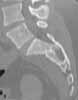

Subject: U-shaped sacral fracture

This is an 18 year old healthy women roll-over ATV with femur fracture now with an antegrade nail. Can I have your advice about this U-shaped pelvis fracture? Injury was pm 5/29.

It appears to be a U-shaped sacral fracture on the limited studies/images...the anterior ring is not shown.

Assuming no other injury in a neuro intact patient, we'd position the patient supine on a sacral support. The sacral support and supine position often improve the reduction...you can use neuro monitoring if you choose. With inlet/outlet/lateral fluoro imaging and according to our preop plan, we'd use bilateral long (130-150mm) iliosacral screws to stabilize the fracture. We'd consider an HTLSO postop.

A "2 levels" screw technique is not helpful in this patient since the injury is confined to the upper-most sacral segment, and is a more dangerous technique since the safe area at the second sacral level is quite small.